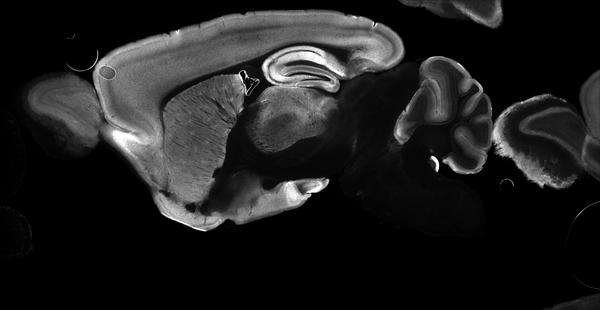

Immunohistochemistry image by Zhuhao Wu, Weill Cornell Medicine

Submitted By: Zhuhao Wu, Weill Cornell Medicine

Addgene Partner

M. musculus (mouse)

Pass